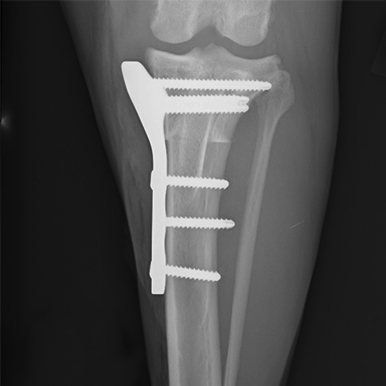

Case Description: The patient is a 13 year old Norwich Terrier diagnosed with a rupture of the anterior cruciate ligament, and received surgical treatment by TPLO.

“The plates of the LeiLOX System provide the opportunity to insert screws at different angles, which is critical in small patients to prevent the screw from entering the joint cavity. The X-ray shows an example of screw insertion at different angles. The video shows the dog walking 2 weeks after the operation.”